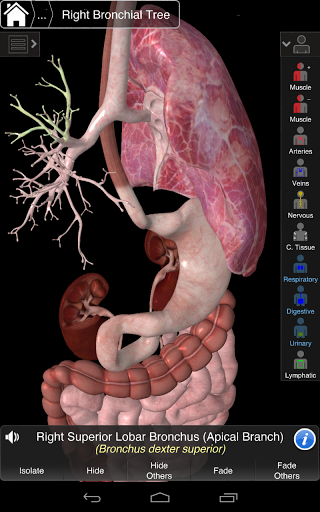

Essential Anatomy 3 reprezentuje najnowsze przełomowe technologie 3D i innowacyjny design. Najnowocześniejszy silnik graficzny 3D, zbudowany na zamówienie przez 3D4Medical od podstaw, zapewnia bardzo dokładny model anatomiczny i zapewnia doskonałą jakość grafiki, której żaden inny konkurent nie jest w stanie osiągnąć.

Aplikacja przedstawia unikalne podejście do uczenia się ogólnej anatomii. Grafika jest nieporównywalna i sprawia, że uczenie się, dzięki wykorzystaniu treści informacyjnej i innowacyjnych funkcji, jest bogatym i wciągającym doświadczeniem.

Ta aplikacja zawiera niezbędną anatomię dla 10 systemów:

⁃Oddechowy

⁃Trawienny

⁃Moczowy

⁃Limfatyczny

Zawiera także mózg i serce

NOWA TECHNOLOGIA 3D

Essential Anatomy 3 jest responsywny, wizualnie oszałamiający i pozbawiony wysiłku. Aplikacja jest w pełni 3D, co oznacza, że możesz zobaczyć dowolną strukturę anatomiczną w izolacji, a także pod dowolnym kątem.

---- Ponad 4000 bardzo szczegółowych struktur anatomicznych

---- Tryb wielokrotnego wyboru - Ukryj / Zniknij / Izoluj pojedyncze lub wiele struktur

---- nomenklatura łacińska dla każdej struktury anatomicznej